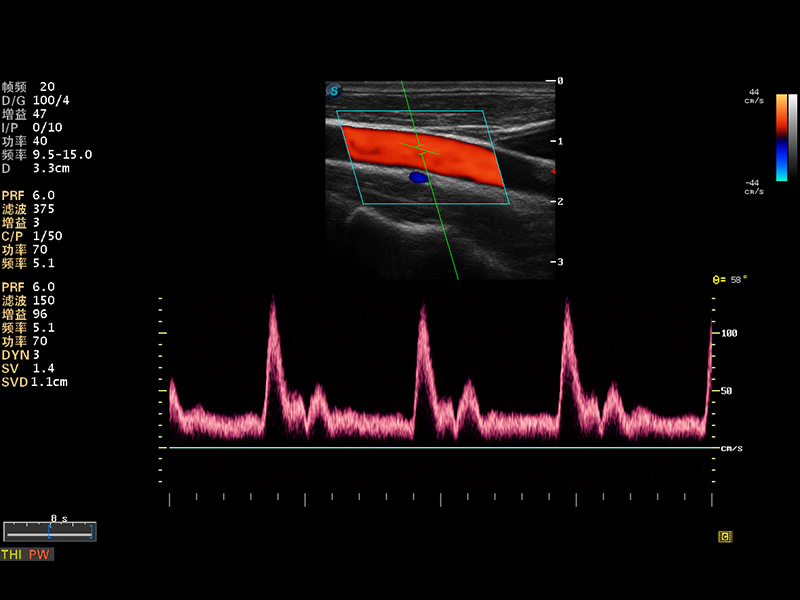

S8 EXP便携式彩色多普勒超声诊断仪是球速体育入口研发的高端全身应用型便携彩超。高通道的VIS平台融合可视化(Visual)、智能化(Intelligent)和人性化(Smart)的特点,配以球速体育入口自主研发生产的探头大家族,使您能够快速、准确的获得病人信息,提高工作效率的同时减轻疲劳。

成像技术

多波束形成器